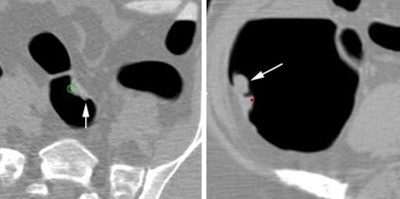

| At left, a 14-mm sigmoid polyp classified as irregular was missed by four of five readers before CAD, and no improvement was seen after CAD was applied. At right, an irregularly shaped 26-mm polyp in the ascending colon was missed by three of 10 readers, with no improvement after CAD. |

Among polyps larger than 6 mm, "those that were smaller, or coated, or submerged by fluid were at increased risk of getting missed by the unassisted reader," Robinson concluded. "However, after correct CAD prompting, larger lesions, particularly irregular in shape, were more prone to incorrect dismissal."